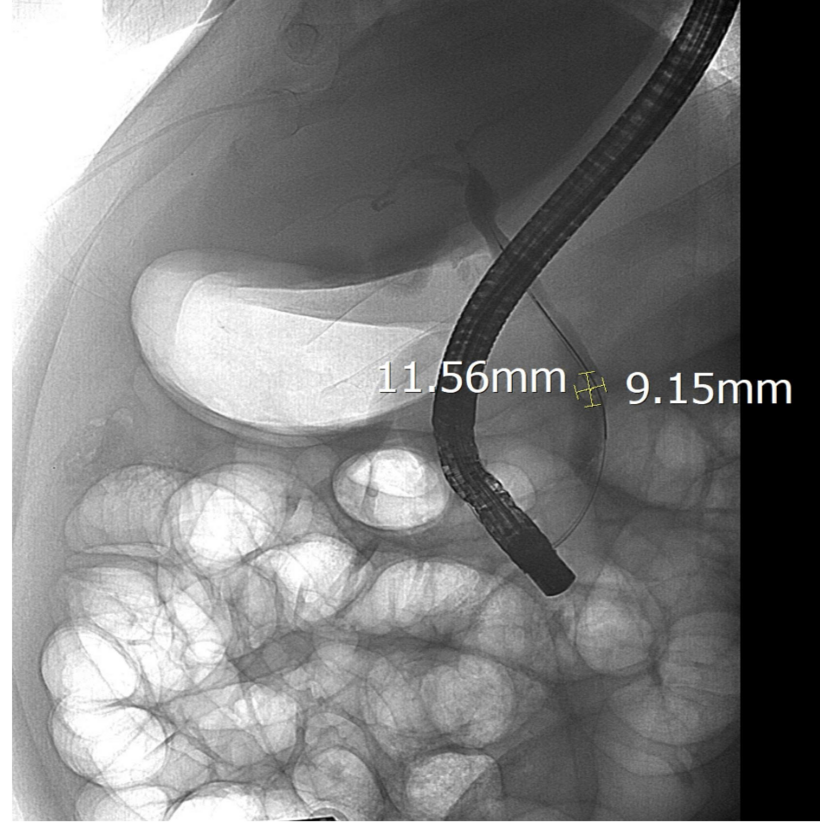

Sỏi ống mật chủ được lộ rõ dưới chụp DSA

Sau khi hội chẩn, các bác sĩ Khoa Nội Tiêu hóa đã chỉ định nội soi mật tụy ngược dòng (ERCP) dưới hướng dẫn của hệ thống chụp mạch số hóa xóa nền (DSA). Trong quá trình can thiệp, ê-kíp đã lấy thành công viên sỏi kích thước 11,5 x 9 mm, giải phóng tình trạng tắc mật.